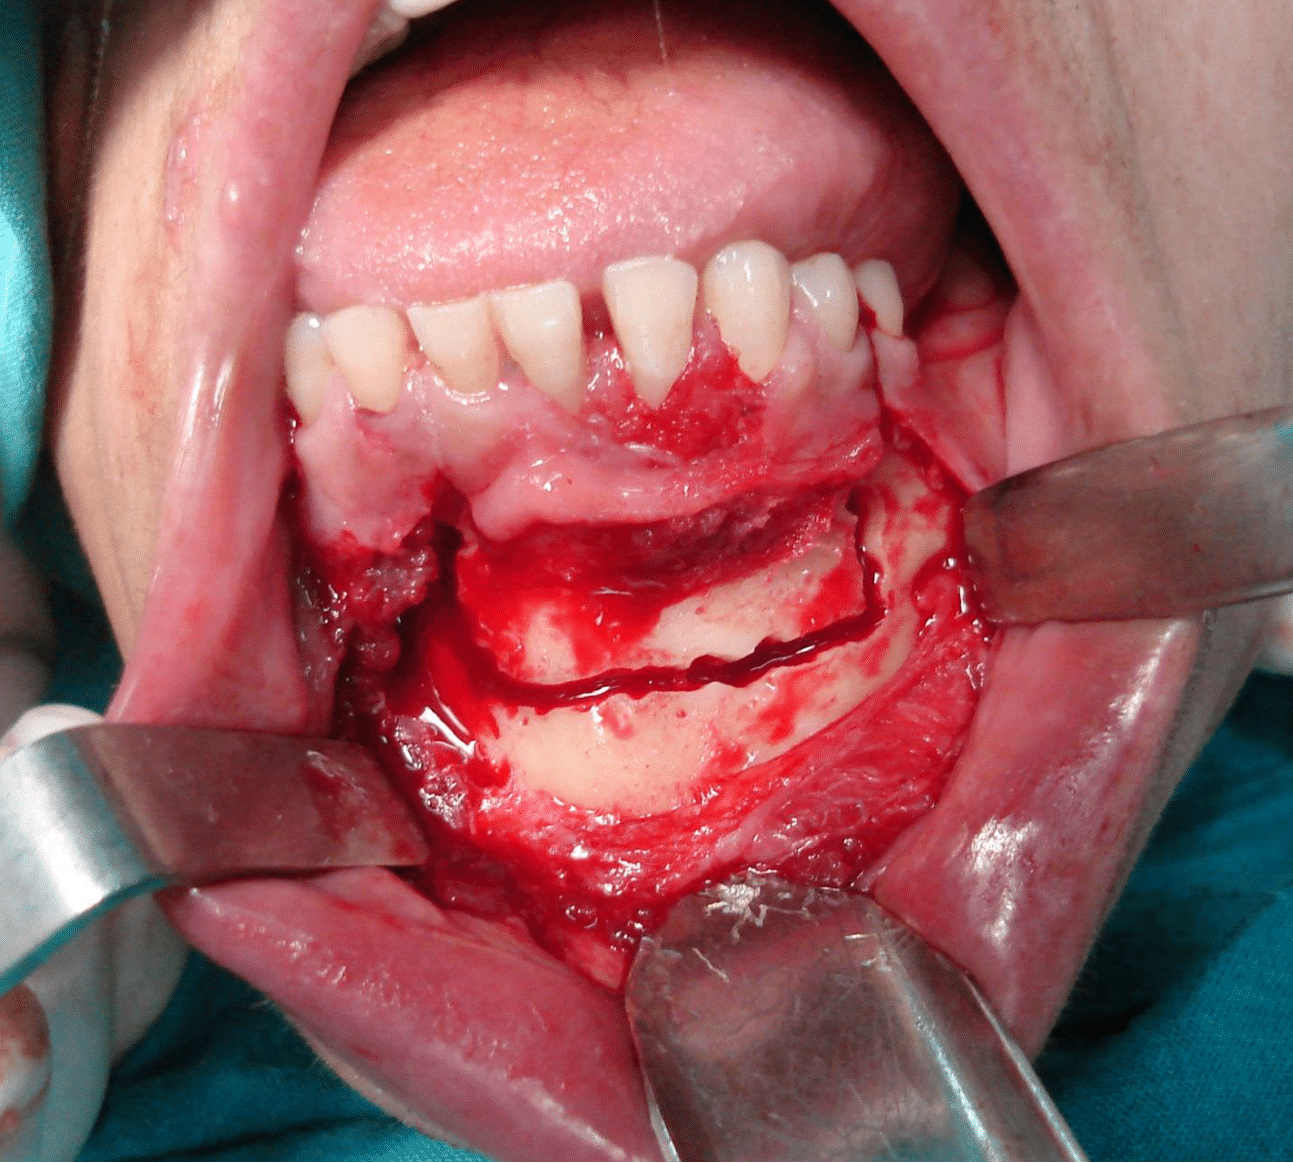

IRB and patient informed consent were obtained. Under general anaesthesia, marginal mandibular resection (alveolar rim resection with preservation of the inferior border) was done with safety margins around all the tissues with clinically evident tumor including the teeth. The safety margin involved the right central and lateral incisors and left canine and first premolar teeth with 0.5 cm of the bone apical to the teeth. A thin osteotome is then used to complete the bony cut through the alveolar process and between the teeth, attempting to maintain the integrity of the soft tissue and avoid damaging teeth. The wound healing was decent, and the soft tissue profile was good (Figure 3A, B, C, and D).

Figure 3a Outline of the mandibular marginal resection with surgical burs.

Figure 3b The resected bony segment.

Figure 3c The mandible after resection of the GSCC.

Figure 3d Postoperative panoramic x-ray view.

Distraction devices were applied to the bone and adapted to accommodate it plates according to the predetermined distraction vector. Then, devices were screwed by drilling bone using 1.5 mm screws. The osteotomy sites were then marked using surgical bur and the devices were removed. The osteotomy is then completed by using a series of osteotomies on the inferior and superior borders and on the lingual aspect. At this point, activation is attempted to ensure movement of the bone segment (Figure 4). The device is then returned to its starting position. The tissue is carefully closed over the device.

Figure 4 Fixation if the distraction to mandible.